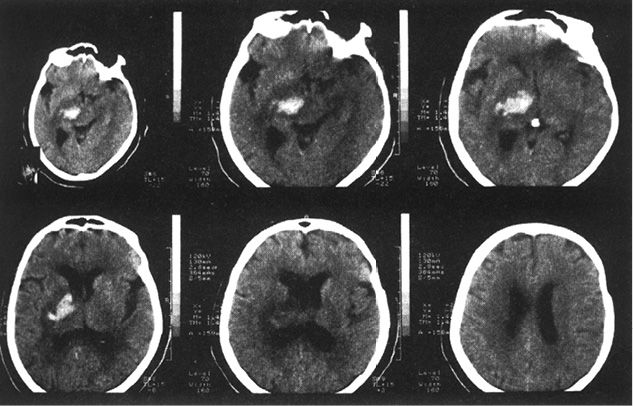

严格地说,松果体并不是大脑的一部分,它也不受血脑障壁的保护。它靠近脑组织的中央区域,这片区域是一个充满液体的空腔,能获得仅次于肾脏的血流量。由于没有血脑障壁的保护,经过一段时间后,液体中的矿物质会聚集成结石,也就是“脑砂”,它具有光学和化学特征,类似于牙釉质。这种钙化现象在X光或核磁共振成像(MRI)下看上去和人骨类似。医生凭借这一坚硬的白色钙化物来判断是否患有脑肿瘤。如果这个白点出现在脑的一侧,则可能是脑肿瘤已经扩散了。

(插图3)X光照片显示左脑室中有个肿瘤。右上方图片中的白点是松果体钙化影,边上的白色区域就是肿瘤的影像。